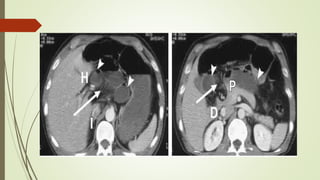

HERNIAS INTERNAS

 Las hernias internas implican la protrusión de las vísceras a través del peritoneo o

mesenterio y en un compartimiento en la cavidad abdominal.

 La presentación más común es una obstrucción intestinal aguda de los pliegues

del intestino delgado que se desarrolla a través de aberturas normales o

anormales.

 Los orificios hernianos responsables son generalmente estructuras anatómicas

preexistentes, tales como agujeros, cavidades y fosas.

 Defectos patológicos del mesenterio y del peritoneo visceral, causados por Los

mecanismos congénitos, la cirugía, el trauma, la inflamación y la circulación, son

también posibles orificios de herniación.

HERNIAS PARADUODENAL.

 Las fosas paraduodenales se originan como anomalías peritoneales

congénitas debido al fracaso de la fusión mesentérica con el peritoneo

parietal y una rotación anormal asociada durante el encarcelamiento del

intestino delgado bajo el colon en desarrollo

HERNIAS PARADUODENAL